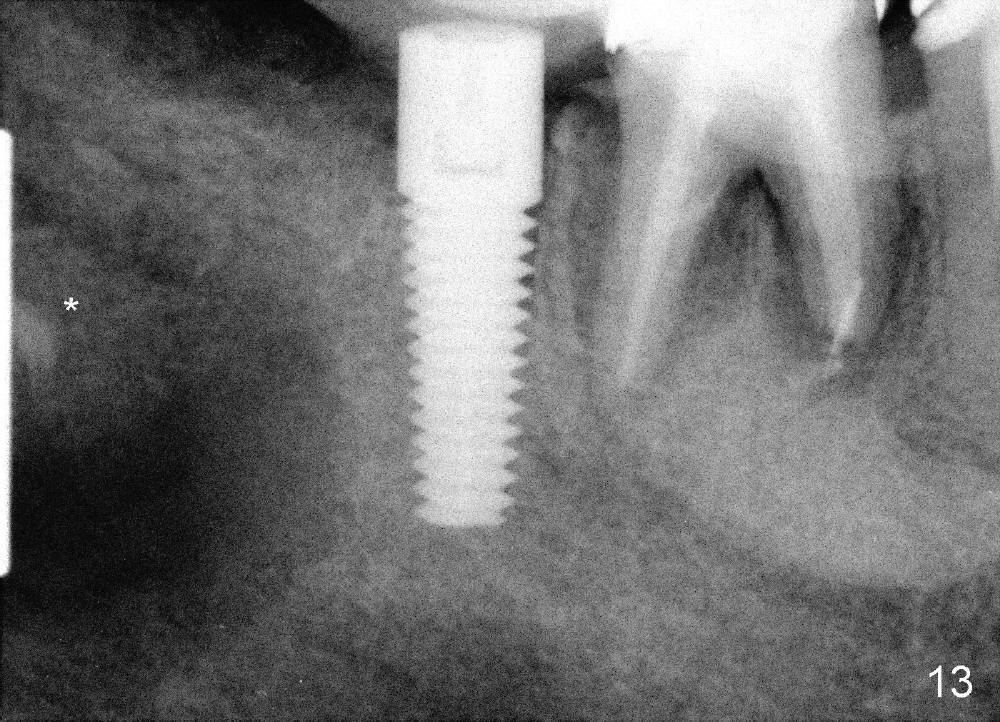

The cystic space is filled by 3 g of allograft (Fig.13 *).